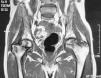

The hip X-ray showed no relevant findings, so we requested a bone scan which showed hypoperfusion of the right femoral head and increased uptake in both ankles suggestive of ON. On MRI we could see multiple bone infarcts of the femoral heads (Fig. 1), proximal regions of both femurs and distal right tibia, astragalus, calcaneus, navicular bone, wedges, cuboid, and metatarsals of both feet (Fig. 2). We indicated a reduction in the weight borne by the lower limbs, but despite this measure the patient developed a major collapse of both femoral heads in a period of 6 months, and is currently awaiting placement of prostheses.